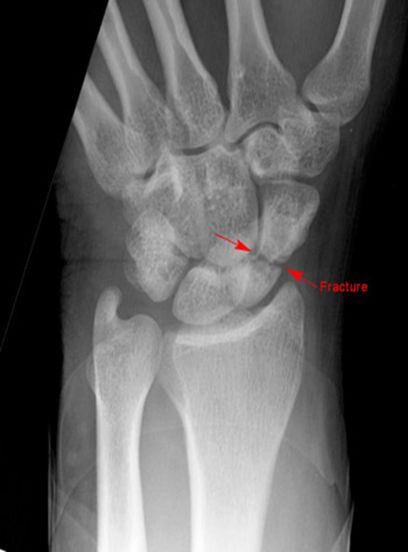

正常腕关节

月骨周围脱位

舟骨骨折

最常见的腕骨骨折

易漏诊

易发生缺血性坏死

儿童少见